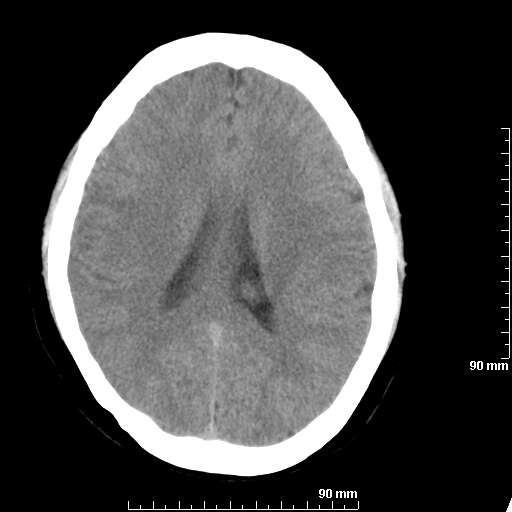

我院西门子单排CT由于一零件受损而产生的伪影.

哈哈,都不是。是虑线器fiter裂损。大家没想到吧。

哦,跟脑出血有点像哦

形状不规则,边缘模糊。比较特殊的一种伪影哈!

这种伪影很常见!伪影应该是在视野的中心的。

西门子的虑线器fiter裂损这才是很难见的问题,GE的最常见

虑线器老化,中间崩裂一块掉了